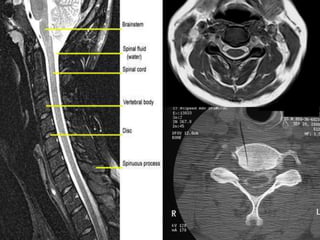

47 year old woman with 6 month h/o neck stiffness and pain with

left UE paresthesias into

The elbow forearm and hand especially IF/thumb

Note:the black line directly posterior to the vertebral bodies and relative

Thinning of spinal cord, note normal disc height

Mid-sagittal diameter: width

1:5 ratio leads to necrosis of gray

matter

• Ogino H: Canal diameter, anteroposterior compression ratio

and spondylotic myelopathy of the cervical spine. Spine 1983;

8:1-15

• Cord compression causes ischemia and direct mechanical

trauma